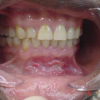

Krooniline gingiviit

Krooniline gingiviit, mida seostatakse katu kogunemisega, esineb enamasti ja on väga tavaline täiskasvanud populatsioonis ning kujuneb välja peale 2-3 nädalast katu ladestumist igemepiirile. Nii nagu on erinevad kõik inimesed on...